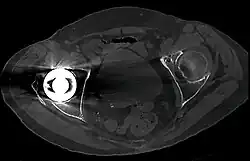

CT scan is widely used for imaging of muscluloskeltal. For the axial skeleton and extremities, CT is often used to image complex fractures, especially ones around joints, because of its ability to reconstruct the area of interest in multiple planes.[74] Fractures, ligamentous injuries, and dislocations can easily be recognized with a 0.2 mm resolution.[75][76] With modern dual-energy CT scanners, new areas of use have been established, such as aiding in the diagnosis of gout.[77]